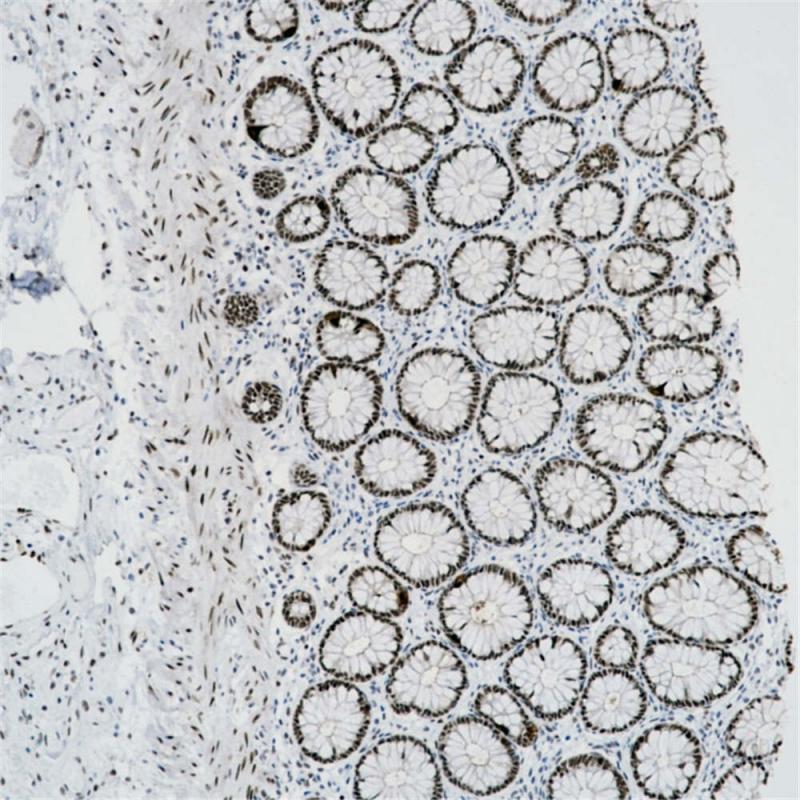

FOXP1 重组兔单克隆抗体

阳性对照

扁桃体

亚细胞定位

细胞核